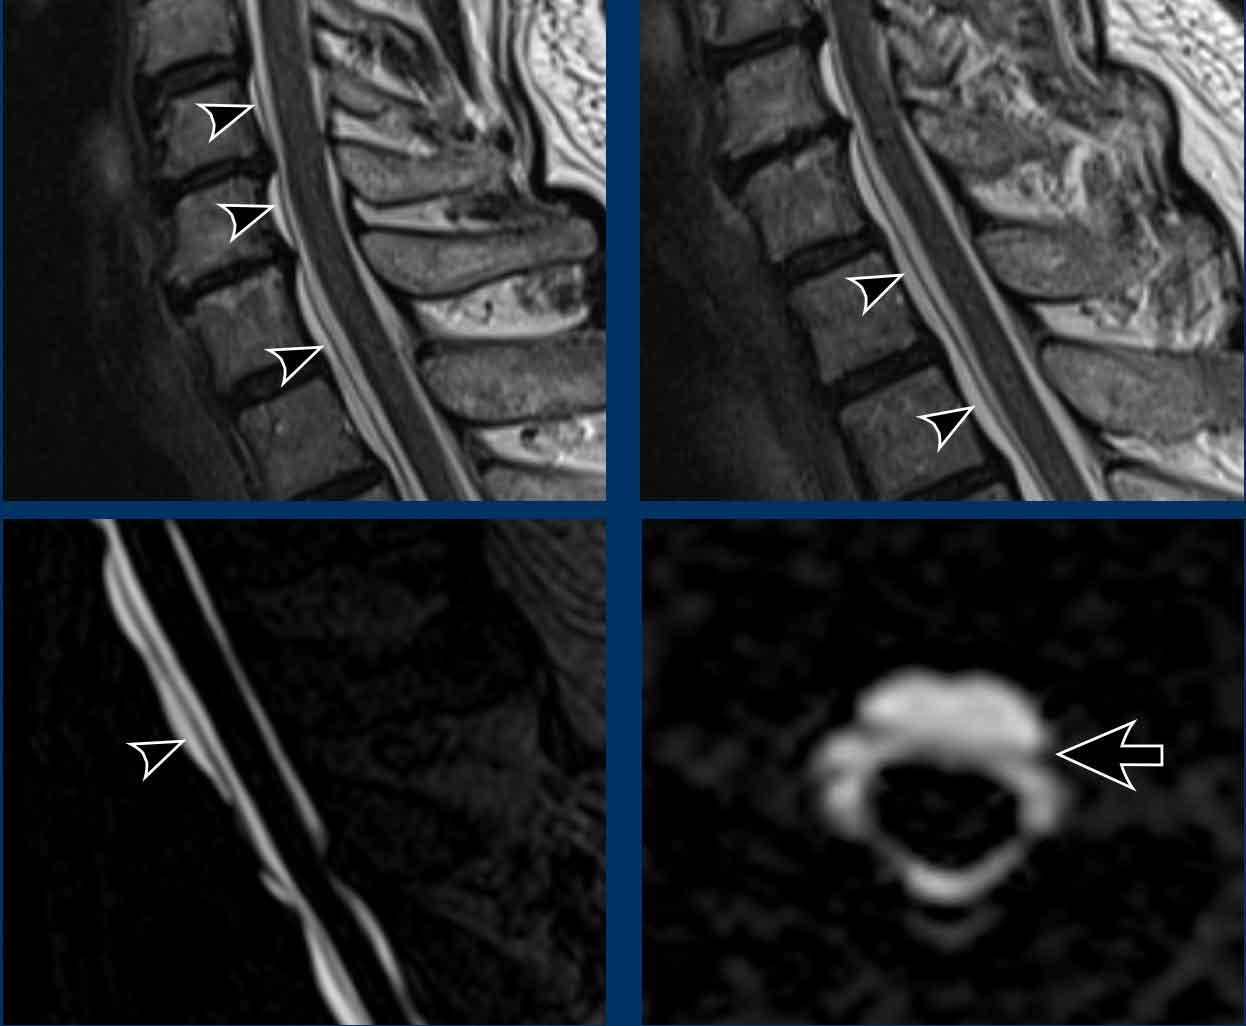

Hình ảnh

- Chuỗi xung T2W sagittal cột sống cho thấy khối tụ dịch dọc phía trước cột sống (SLEC), nằm ngay phía trước màng cứng mặt trước (cấu trúc tuyến tính màu đen được chỉ bởi các đầu mũi tên).

- Chụp tủy đồ CT thông thường (thực hiện sau chụp tủy đồ động) cho thấy hai thoát vị đĩa đệm vôi hóa một phần ở đoạn cột sống ngực trên (mũi tên).

Trên chụp tủy đồ CT thông thường, có hiện tượng rò rỉ thuốc cản quang iod vào khoang ngoài màng cứng phía trước.

Lưu ý rằng dấu hiệu này chỉ thấy được trên các lát cắt axial tái tạo (đầu mũi tên).

Trên các lát cắt sagittal, dấu hiệu tinh tế này có thể bị bỏ sót.